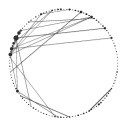

The pathways specific to early PD show a great involvement of the immune system, which is greatly stimulated by inflammation especially located in particular brain regions (mainly substantia nigra). Indeed, we identified: GO:0006952 i.e. defense response, GO:0045087 i.e. innate immuno response also visualized in Figure 3, GO:0006955 i.e. immune response and GO:0030097 i.e. hemopoiesis.

|

| (a) early PD patients | (b) controls |

From Figure 3 it is clear that since the early stages of PD the innate immune system is severly compromised: the body is highly subjected to the invasion and proliferation of microbes (like bacteria or viruses), resulting in a debilitated organism, less effective in fighting the consequent inflammation.